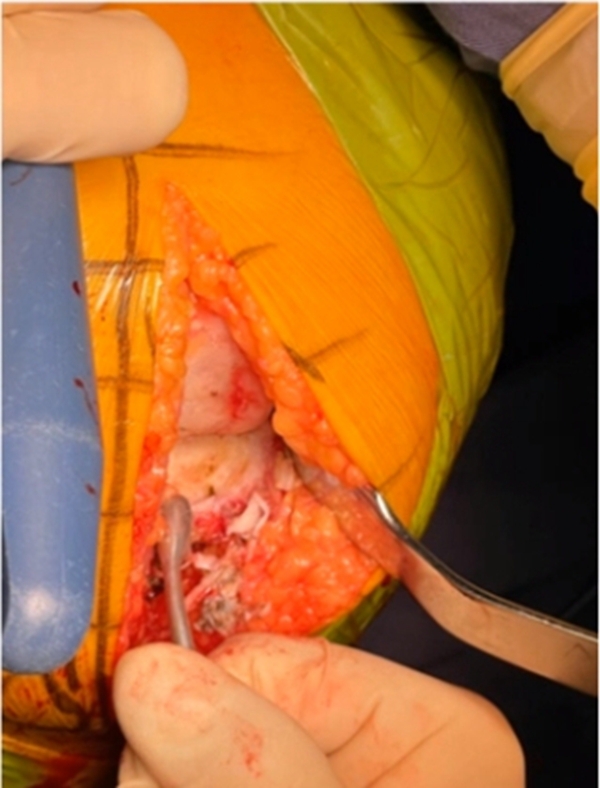

此时要把股骨髁间窝外侧壁进行整个的骨赘去除,但是对于股骨内侧髁外侧壁的骨赘一定不要去除。随后常规插入髓腔杆,它主要目的是髌骨拉钩的作用,能够提高整个手术的效果。然后要剥离股骨内侧髁内上方贴附区的软组织,刮除股骨远端贴附区软骨。注意不要去除周围的骨赘,但是骨赘表面的软骨一定要去除。

5、胫骨准备

胫骨准备也是也是一样的要求,参照导板在模型上表面紧密贴附的位置去除残余的软骨。注意不要先清除胫骨前方的骨赘,可以将前又韧带止点前方的砧状骨赘去除。同时要清除髁间窝内侧壁的骨赘。

6、贴附胫骨导板

将胫骨导板置于剥离显露好的骨面,术者通过按压点向后、下、外施压,令导板与胫骨前、上和胫骨结节内侧充分贴附。按照顺序打导针,此时要注意术者按压,助手打导针,确保导针与固定孔的方向保持一致,并且导针突破二次阻力就停,不要导针过深导致后边血管神经损伤。